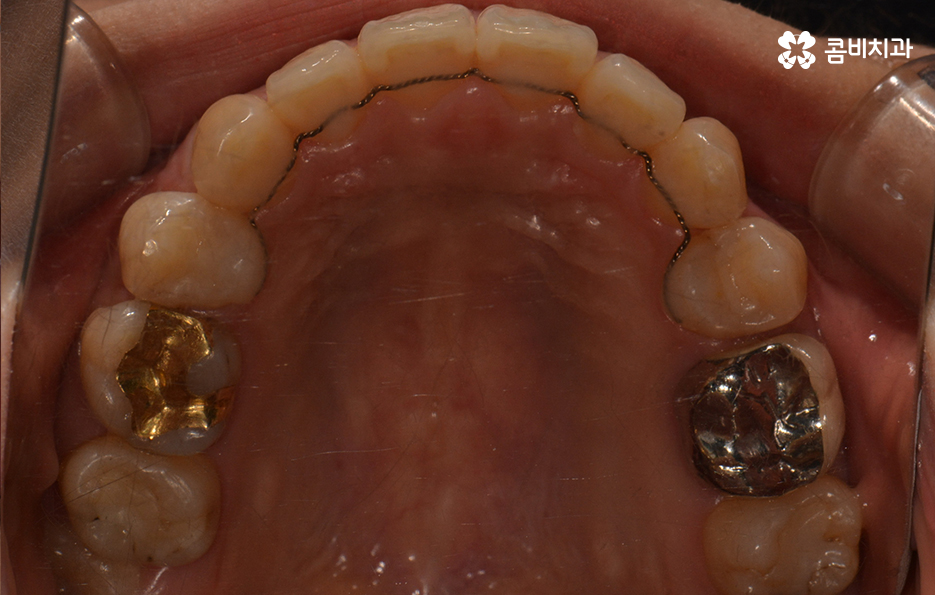

윗니가 설측으로 시술이 진행되고 있는 모습이며

발치를 한 부위 안쪽으로 치아가 이동하기 때문에

돌출입의 개선이 함께 이뤄지며 치열뿐 아니라

얼굴과 자연스럽게 어울리는 결과를 얻을 수 있습니다.

교정 장치를 풀어낸 후 유지 장치를 부착하고 있는 모습